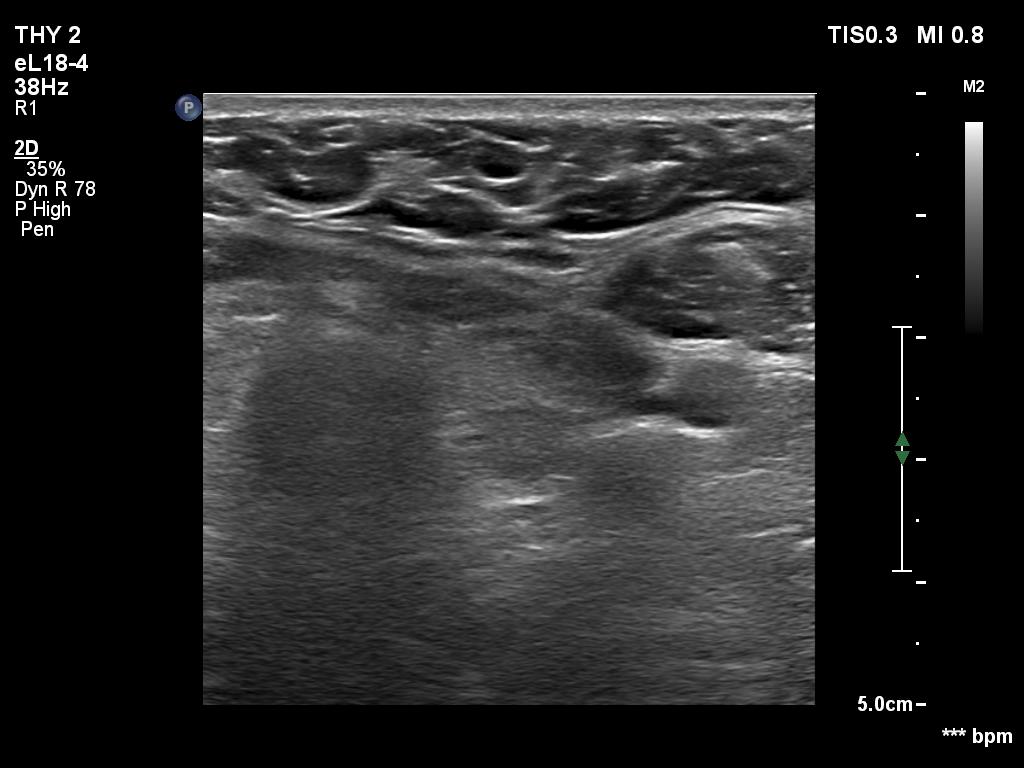

Ultrasonography. The thyroid was echonormal. Using higher frequency three discrete hypoechoic lesions were found, one in the middle dorsal part of the right lobe, one in the middle and a third one in the lower dorsal part of the left lobe. By decreasing the frequency, the presence of only the third one could be confirmed.

FNA of the nodule in the lower dorsal part of the left lobe resulted in benign colloid goiter.

Comment. It is a rule that larger the distance from the probe worse the permeability of ultrasound wave. This can lead in certain patients (overweighted ones or frequently in men) that the dorsal part of the thyroid lobe can deceptively look darker, i.e. hypoechoic. If we have any doubt, by lowering the frequency i.e. increasing the penetrance, the real situation can be much better to judge.

This happened in this patient. If we would trust the pattern gained by higher frequency settings, we would falsely diagnose at least one additional nodule.